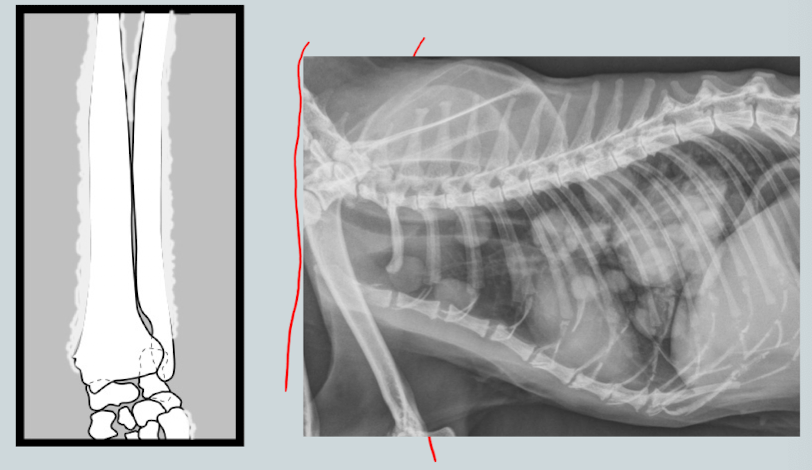

________________: neoplastic sydrome of unknown etiology affecting middle-older dogs. Will see periosteal reaction of digits/long bones associated with neoplastic or infectious lung disease. Distal limbs.

Hypertrophic osteopathy (Maries disease)

What are the arrows pointing to?